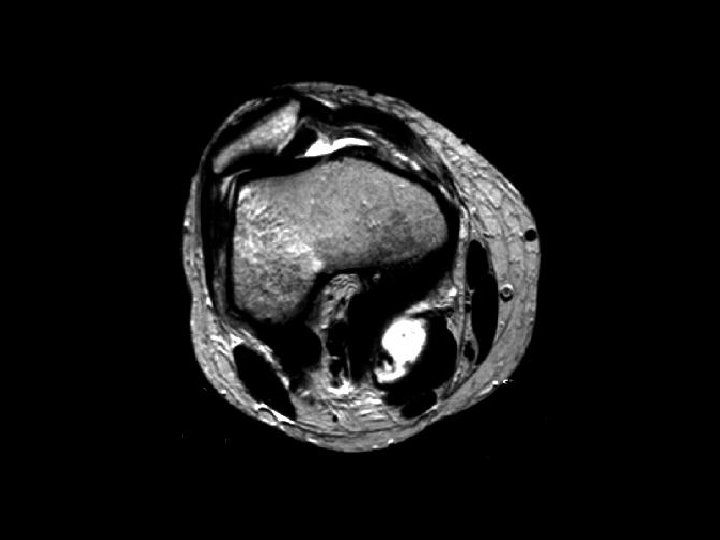

Bucket-Handle Tear • • Findings: – “double PCL sign” - torn meniscus BELOW normal PCL on sag view – Above ACL on cor view – Truncation of medial meniscus – Joint effusion Medial = 3 x lateral Locked knee ddx: – torn ACL, PCL – torn meniscus